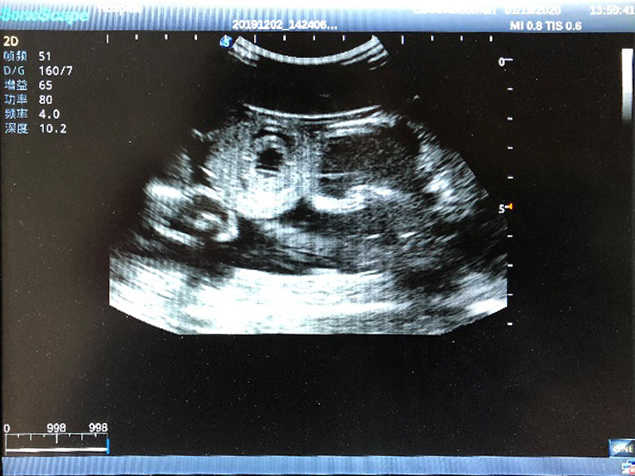

2) High quality ultrasound image with clear structures like gallbladder, liver, intestines, arteries and veins etc.

4) ltrasound gallbladder pathologies like cholecystitis, gallstone and polypoid degeneration

5) Normal & pathological ultrasound live and intestine models inside